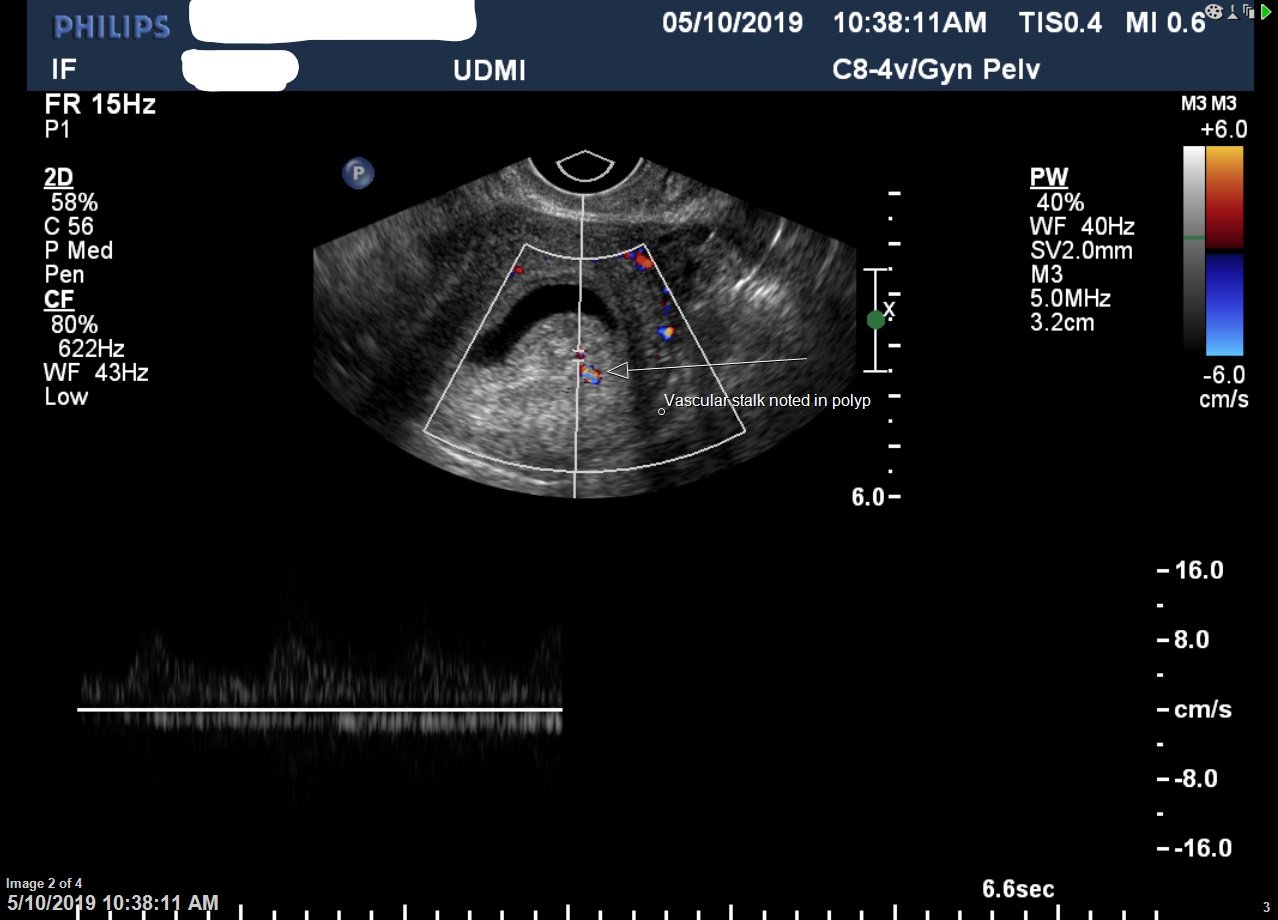

hysterosonogram

Home » Hysterosonogram: Uses, Benefits, What to Expect, FAQs » hysterosonogram